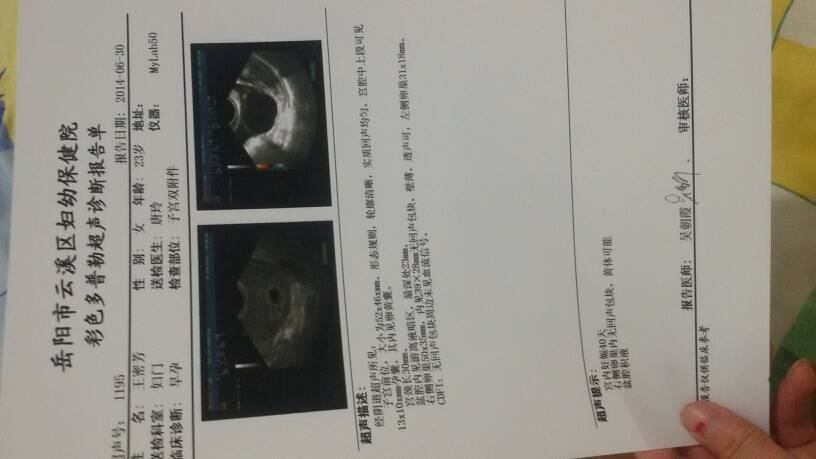

有盆腔积液的表现,一般不会影响胎儿的,定期检查胎儿发育情况,发现问题及时处理,